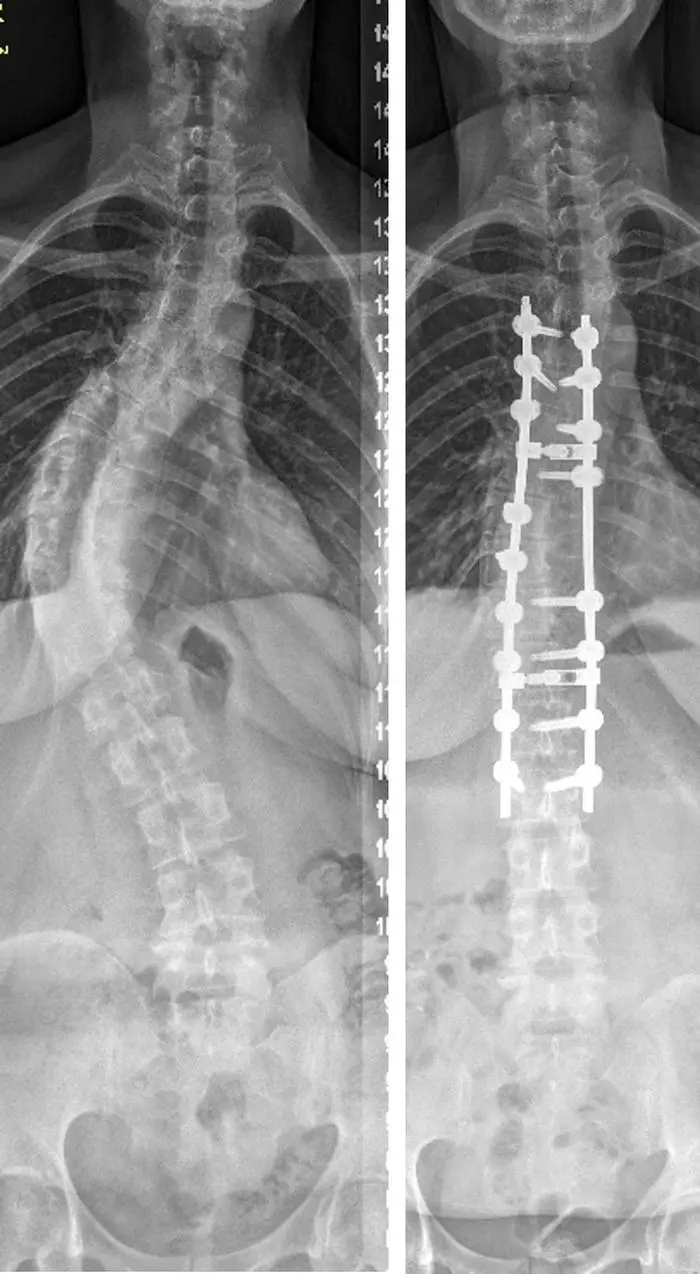

Verkrümmte Wirbelsäule: Warum man Skoliose behandeln sollte, bevor sie schmerzt

Heute ist der Tag der Wirbelsäule: Skoliose beschreibt die Verkrümmung der Wirbelsäule. Wie man die Erkrankung frühzeitig erkennt, welche Therapien wann wirken.

• Skoliose beschreibt die Verkrümmung der Wirbelsäule, die oft im Alter von 10 bis 12 Jahren beginnt und frühzeitig erkannt werden sollte, um sanfte Therapiemöglichkeiten zu nutzen.

• Bei leichten Verkrümmungen (unter 40 Grad) sind Korsett und Physiotherapie die bevorzugten Behandlungsoptionen, um eine Verschlechterung zu verhindern.

• Operationen, insbesondere Versteifungs-OPs, sind oft die einzige Option bei schweren Verkrümmungen (über 50 Grad), wobei das Risiko für neurologische Komplikationen unter 1 Prozent liegt.

• Neue Methoden wie wachstumsfreundliche Implantate bieten bei kleinen Kindern eine Alternative zur Versteifung, um das Wachstum der Wirbelsäule zu lenken.